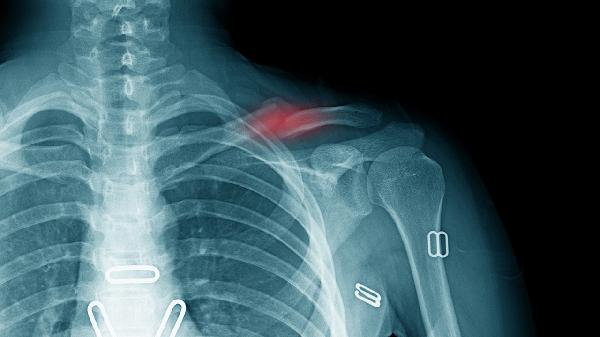

游離骨塊是骨骼損傷后脫離正常位置的骨組織碎片,由于缺乏血液供應和固定支撐,難以通過(guò)人體自然吸收機制消除。較小的游離骨塊可能被纖維組織包裹形成穩定狀態(tài),但完全吸收的概率較低。若骨塊位于關(guān)節腔內,可能引發(fā)機械性卡壓、慢性滑膜炎或繼發(fā)骨關(guān)節炎,表現為關(guān)節交鎖、反復腫脹及進(jìn)行性功能障礙。影像學(xué)檢查可明確骨塊位置和大小,醫生會(huì )根據具體情況選擇關(guān)節鏡取出、開(kāi)放手術(shù)清理或藥物緩解癥狀等方案。